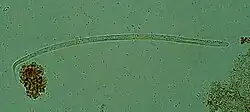

| Onchocerca volvulus, the causative agent of river blindness | |

Onchocerca volvulus parasites obtain nutrients from the human host by ingesting blood or by diffusion through their cuticle. They may be able to trigger blood-vessel formation because dense vascular networks are often found surrounding the worms.[6] They are distinguished from other human-infecting filarial nematodes by the presence of deep transverse striations.[7]

It is a dioecious species, containing distinct males and females, which form nodules under the skin in humans. Mature female worms permanently reside in these fibrous nodules, while male worms are free to move around the subcutaneous tissue. The males are smaller than females, with male worms measuring 23 mm in length compared to 230–700 mm in females.[7]

The release of oocytes (eggs) in female worms does not depend upon the presence of a male worm, although they may attract male worms using unidentified pheromones.[8] The first larval stage, microfilariae, are 300 μm in length and unsheathed, meaning that when they mature into microfilariae, they exit from the envelope of the egg.[9]